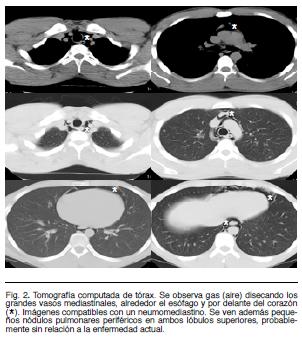

Se trata de un paciente de sexo masculino, de 18 años de edad, tabaquista leve. Consulta por dolor retroesternal de aparición en reposo, de 6 horas de evolución, opresivo, que irradia a cuello y aumenta con la inspiración profunda. Sin fenómenos acompañantes. Sin traumatismo de tórax, ni consumo de tóxicos inhalados previo al inicio de los síntomas. Del examen clínico se destaca: taquicardia regular de 100 cpm, con presión arterial de 120/70 mm Hg. Examen pleuropulmonar: normal. Electrocardiograma: taquicardia sinusal de 100 cpm. Radiografía de tórax (Figura 1) evidencia imagen lineal radiolúcida que rodea el borde izquierdo del mediastino. Se completa el estudio radiológico del tórax con una tomografía computada (Figura 2) en la que se evidencia gas (aire) disecando los grandes vasos mediastinales, alrededor el esófago y por delante del corazón.

Se presenta un caso de neumomediastino espontáneo. Las características epidemiológicas (edad de presentación, sexo), son concordantes con la literatura. No se encuentran factores desencadenantes en el caso relatado. En la literatura se identifican como desencadenantes todos aquellos factores que determinen un aumento de la presión intrapulmonar: acceso de tos, crisis asmática, vómito, maniobra de Valsalva, trabajo de parto, etc. Se ha asociado además al uso se cocaína, marihuana y éxtasis entre otros(3-5,8-10). La presentación clínica es heterogénea. Los síntomas más frecuentes son dolor torácico (presente en este paciente y en 63-89% de los casos según la serie) y disnea de intensidad variable (44-60%). Otros síntomas descritos son disfagia (3-67%), dolor generalizado de cuello (11-18%) y disfonía (5%), no presentes en el caso analizado(2,3,5-7,11,12). Los hallazgos clínicos más frecuentes son la presencia de enfisema subcutáneo en la escotadura supraesternal y el denominado signo de Hamman (40-80%) dado por la crepitación sincrónica con la sístole a nivel retroesternal, auscultándose mejor en decúbito lateral izquierdo(2,11,12). La presencia de pulso paradojal por aumento de la presión mediastínica es infrecuente(9). En el caso relatado el examen clínico es normal a excepción de la presencia de taquicardia sinusal. El diagnóstico de NE requiere un alto índice de sospecha, lo que determina que no sea considerado entre los planteos diagnósticos iniciales en un paciente joven con dolor torácico. En la radiografía de tórax se puede objetivar el signo del diafragma continuo (aire entre el pericardio y el diafragma), neumopericardio (aire anterior al pericardio en la radiografía lateral de tórax), signo de la V de Naclerio (aire entre la aorta descendente y el hemidiafragma izquierdo), resalte del contorno cardíaco y aire a nivel subcutáneo(2,11,13). La presencia de una columna estrecha e hiperclara en el mediastino y rodeando la silueta cardíaca es un hallazgo frecuente presente hasta en 90% de pacientes en algunas series (14). La tomografía computada de tórax permite confirmar el NE, valorar la extensión y descartar patologías asociadas(3,11). Los diagnósticos diferenciales a descartar son otras causas de dolor torácico que asocien enfisema subcutáneo como la perforación esofágica (síndrome de Boerhaave) y el neumotórax espontáneo(3,4). El tratamiento es habitualmente conservador en base a reposo, analgésicos y antitusígenos , como lo es el caso analizado. De haber compresión de las estructuras mediastínicas se puede realizar aspiración con aguja o por un catéter percutáneo colocado en el mediastino(15). En la mayoría de los casos el curso es benigno y autolimitado con reabsorción del aire ectópico en pocos días como sucedió en el caso descrito. En 9-16% la evolución puede ser fatal. Las recidivas son inhabituales(2,3,11).